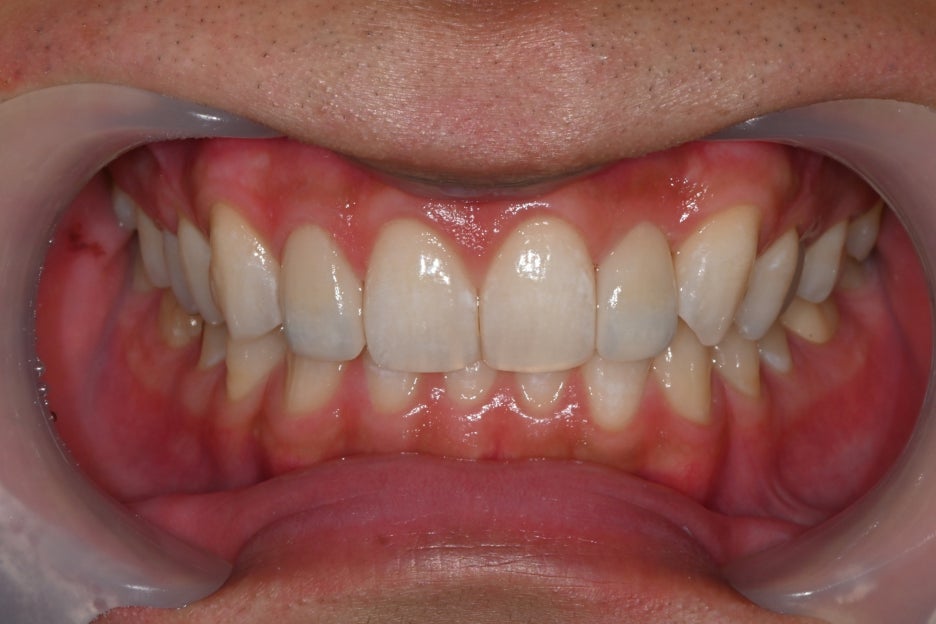

오브제로 라미네이트 부착

-자연스러운 앞니 완성

최종 접착은 강도와 안정성이

검증된 재료를 사용해 진행했습니다.

<접착 후>

교합 조정

미소 라인 확인

외부 사진 촬영

을 진행해 완성도를 체크했습니다.

장착 직후부터 환자분은

티 나지 않고 원래 제 치아인듯

너무 자연스러워요

만족해하셨습니다.